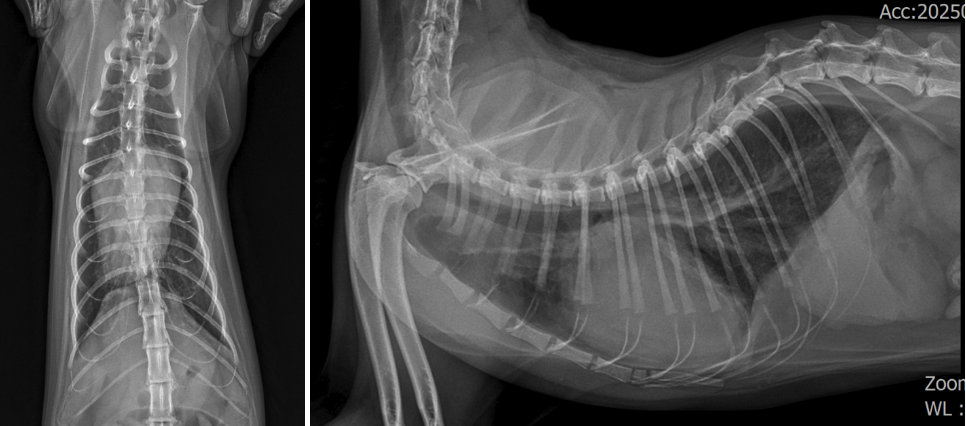

내원 시 흉부방사선 검사/ 출처: 24시온숲동물의료센터

흉부 방사선 검사: 2살의 어린 나이임에도 불구하고 심장이 비정상적으로 크게 비대되어 있었습니다.